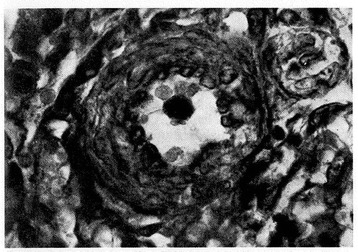

Figure 10.

Pulmonary arteriole from a small for date newborn who died at 2 days of life from esophageal atresia. Marked thickening of medial muscle mass is evident (H.E. stains). From Distefano G et al. [12], Med Surg Ped 1992. (Personal observation).